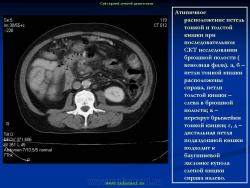

Варианты и аномалии развития толстой кишки.